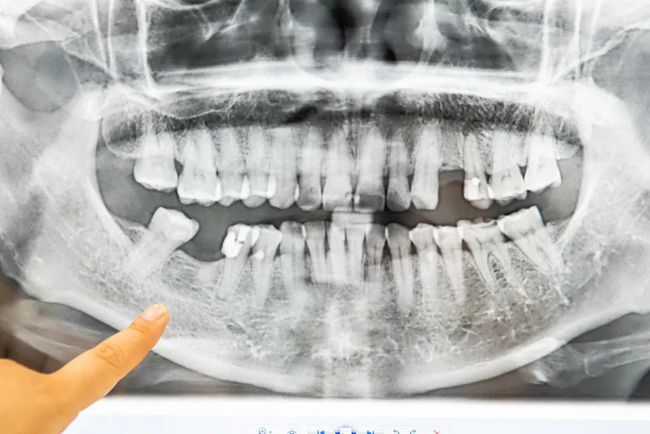

单牙缺失

种植后

多颗缺失

前后对比图